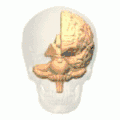

-

Position of marginal sulcus (shown in red). -